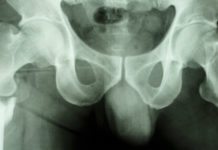

Forskarna har granskat omkring 5 300 röntgenbilder av lårbensfrakturer bland vilka de identifierade 172 stycken så kallade stress- eller atypiska frakturer. Uppgifterna samkördes med läkemedelsregistret och forskarna såg då ett samband mellan användning av bisfosfonater och stressfrakturer.